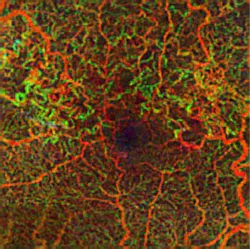

Zeiss Medical Technology (Dublin, CA) has received FDA clearance for its AngioPlex OCT angiography technology, which enables ophthalmologists to use optical coherence tomography (OCT) images to assess the blood vessels (vasculature) of the retina at a depth and clarity never available before. The technology delivers high-resolution, depth-resolved visualization of the separate layers of the retinal and choroidal vasculature without the need for an injected contrast dye, as is standard with fluorescein angiography (FA).

The information provided by these images is clinically impactful, because progression of retinal diseases is often accompanied by changes in the vasculature of the eye. In age-related macular degeneration (AMD), diabetic retinopathy, central retinal vein occlusion, and other vascular conditions, AngioPlex OCT angiography can complement traditional FA and become a safe and efficient part of routine eye care, potentially enabling earlier detection and management of micro-progressions.

AngioPlex OCT angiography clearly visualizes blood flow by detecting motion of scattering particles, such as red blood cells, within sequential OCT B-scans performed repeatedly at the same location of the retina. Unlike other OCT angiography systems that require multiple OCT scans to generate one single OCT angiography image, the company's CIRRUS HD-OCT system with AngioPlex only requires a single additional OCT scan. The key to this is the real-time retinal tracking system, FastTrac, that actively eliminates eye motion to provide motion-artifact-free images of the perfused retina. Equally important, FastTrac enables follow-up OCT angiography images to be acquired at the same precise location to assess treatment efficacy and monitor disease progression.